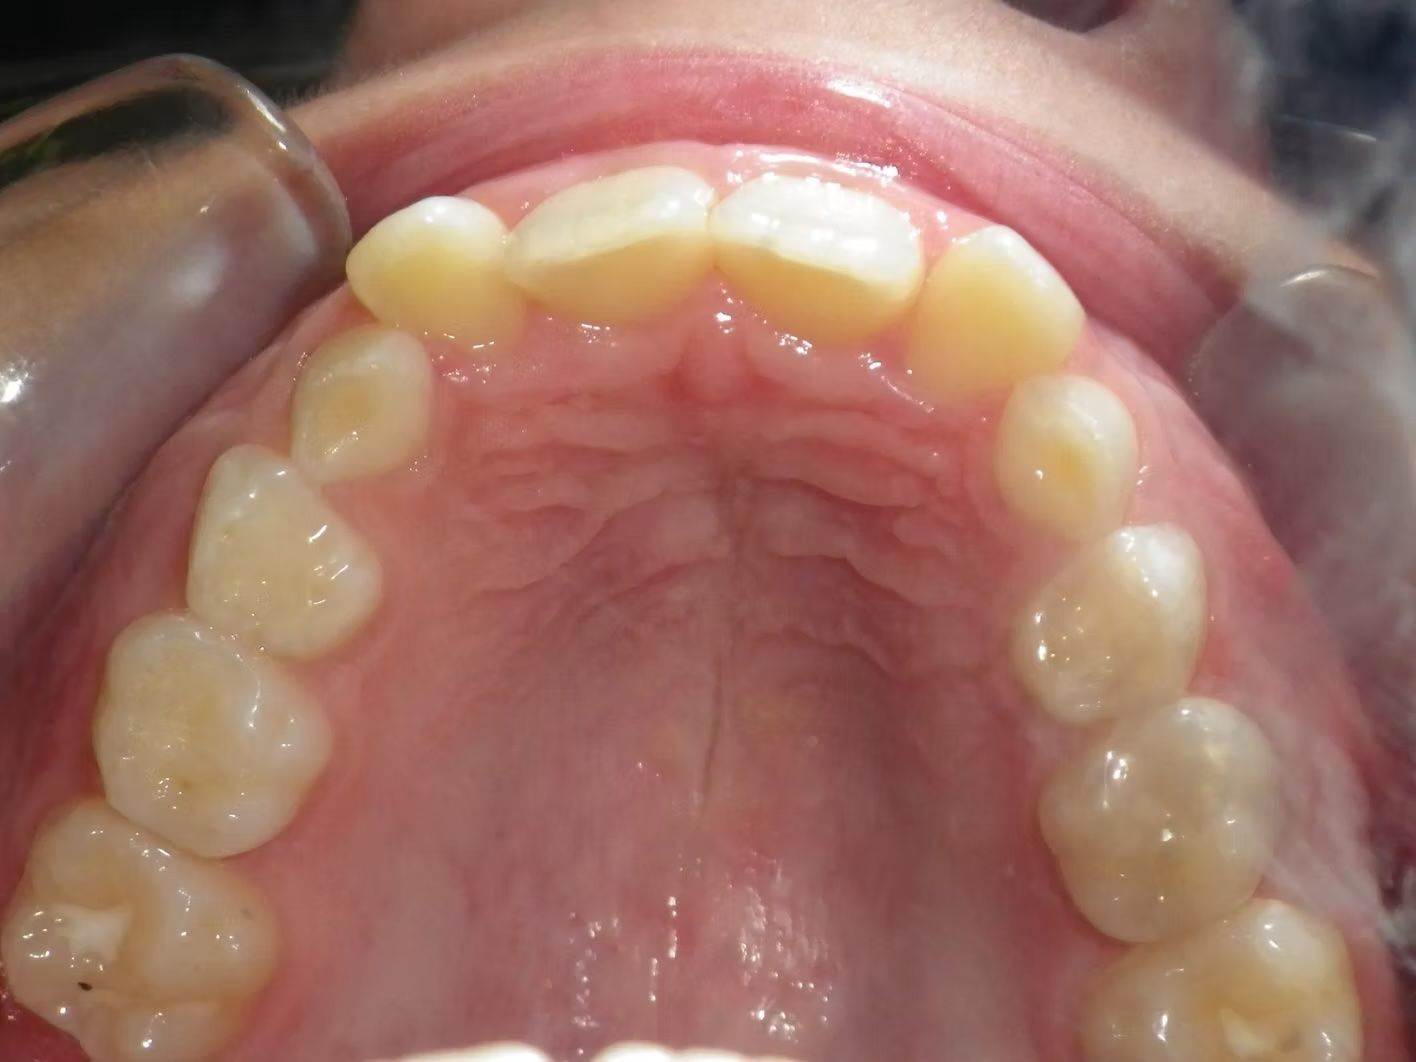

Imset

Imset came to see Dr. Bret because he felt like the upper and lower teeth were too crowded. The lower canines were in cross-bite with the upper teeth and there was significant crowding in the lower arch. He previously had 2 teeth pulled in the top and at the time none in the bottom. This made the top jaw smaller than the lower and the lower teeth didn't have room to fit inside the top teeth. We had 2 lower teeth extracted, and then aligned the upper and lower teeth to fit excellently together- no more crowding!